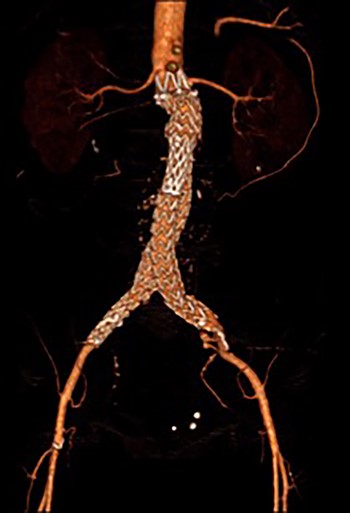

3D reconstruction CT scan, at 6-week interval from index procedure.

The patient was transferred to the high-dependency unit for observation during the thrombolysis. After 4-h, the patient was taken back to Interventional Radiology department for a check angiogram (Fig. 3). This demonstrated a fully re-canalized aorto-iliac system with no distal thrombotic or embolic complications. The thrombolysis infusion was stopped at this stage. In the post-operative period, anticoagulation has been continued with Apixaban. A CT scan 6 weeks post-procedure has confirmed ongoing patency of the endograft with no visible thrombus (Fig. 4).